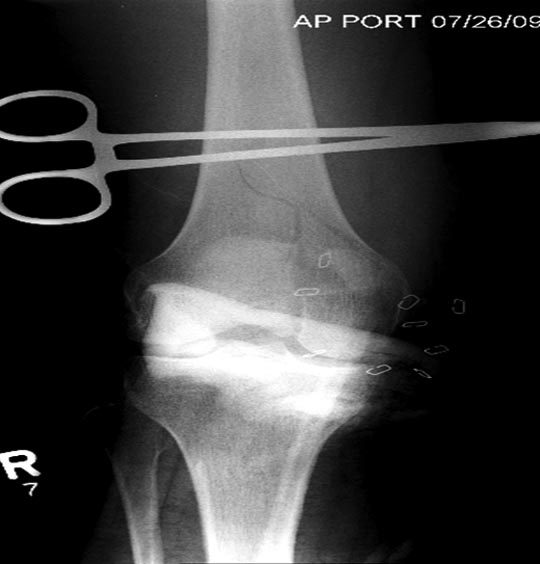

Здесь перечислены ортопедические повреждения: Rt. femoral shaft fracture, Rt femoral head fracture-dislocation, Rt distal femur fracture, Rt. open patella fracture, Rt. talus fracture dislocation, Rt. open humerus fracture, Left 5th metatarsal fracture, Left dislocation 1st TMT.

На 9й день фиксация дистального бедра, где фрагмент Hoffa и вертикальный перелом надколенника, зафиксированы винтами.

Раны в области коленного сустава и на плече до сих пор чистые, остаются открытыми. Отсутствует признаки инфекции, решили превратить недостаток в преимущество, т.е. фиксировать через открытые раны пластинами.